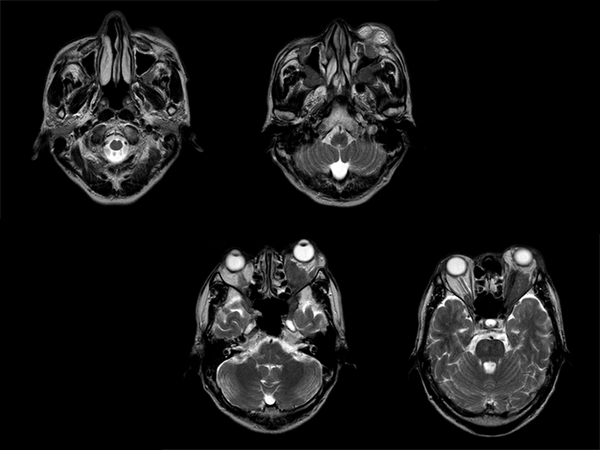

診断:下垂体炎、硬膜炎、三叉神経の炎症性偽腫瘍

【画像所見】

眼瞼腫脹と視力低下

見るからに眼窩内偽腫瘍 + 三叉神経の腫大

T2強調画像

下垂体炎、硬膜炎、三叉神経の炎症性偽腫瘍